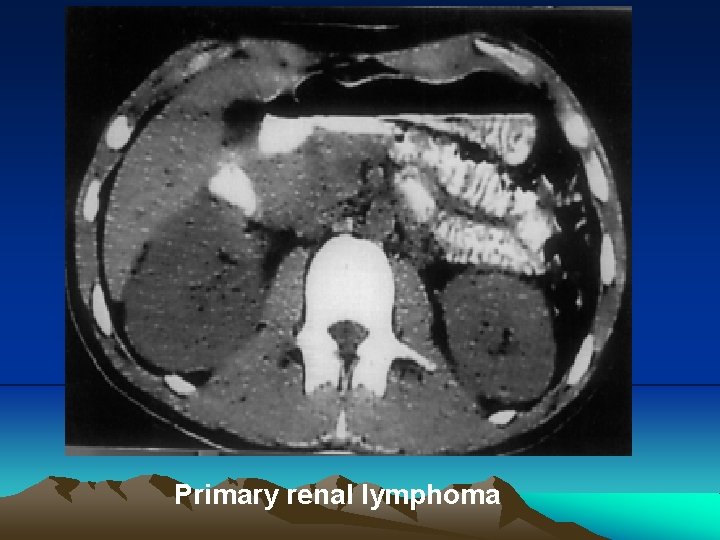

Renal lymphoma has an insidious clinical presentation that occurs late in the course of the disease. It can present in many ways, however the most common are primary tumors presenting single or multiple nodules, or that involve the kidney, either in a hematogenic dissemination form or through a contiguous retroperineal disease

Primary renal Iymphoma